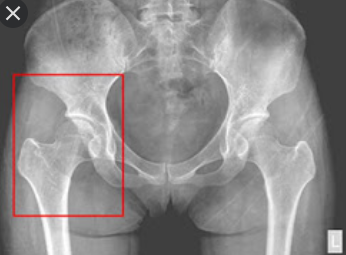

고관절은 골반과 대퇴골을 이어주는 관절입니다. 그래서 엉덩이관절, 엉덩관절 등 여러명칭으로 불리고 있습니다. 고관절이 불편하거나 통증이 있다면 하체를 움직이기에 불편함이 커집니다.

고관절 골절

모두들 아시듯이 고관절이 외상으로 인해 골절이 생기는 경우입니다. 보통 중장년층이상이나 노인 분들이 뼈의 강도가 약해지는 골다공증으로 인해 가벼운 넘어짐으로도 쉽게 발생합니다.

선천성 고관절 탈구

태어날 떄 부터 고관절이 어긋나는 질환입니다. 오리걸음으로 걷는 경우가 많고 제대로 치료받지않는다면 관절에 염증이 많이 생겨 퇴행성 관절염이 생깁니다.

대퇴골두 무혈성괴사

쉽게 말해서 고관절 근처의 혈액순환에 문제가 생겨서 대퇴골 머리 부분에 혈액이 제대로 공급되지않게 됩니다. 이럴 경우 혈액이 공급되지 않아 뼈가 썩게 됩니다.

퇴행성 고관절염

흔한 질병으로 노화나 관리를 하지 않아 발생되는 질명으로 관절을 많이 사용하다보니 연골이 닳게 됩니다. 그래서 염증이 생기고 뼈와 뼈가 부딪히면서 통증을 유발하게 됩니다.